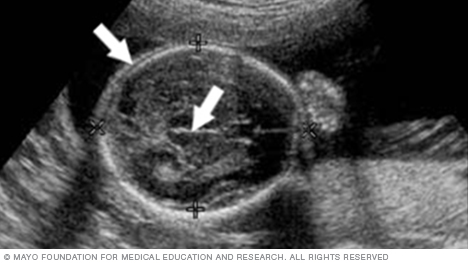

Below is a view of a fetus's head. The thicker white lines that form a circle are the skull. The white line in the middle of the circle is the midline structure that separates the baby's brain into its right and left halves. Head measurements can help determine the age of a fetus.